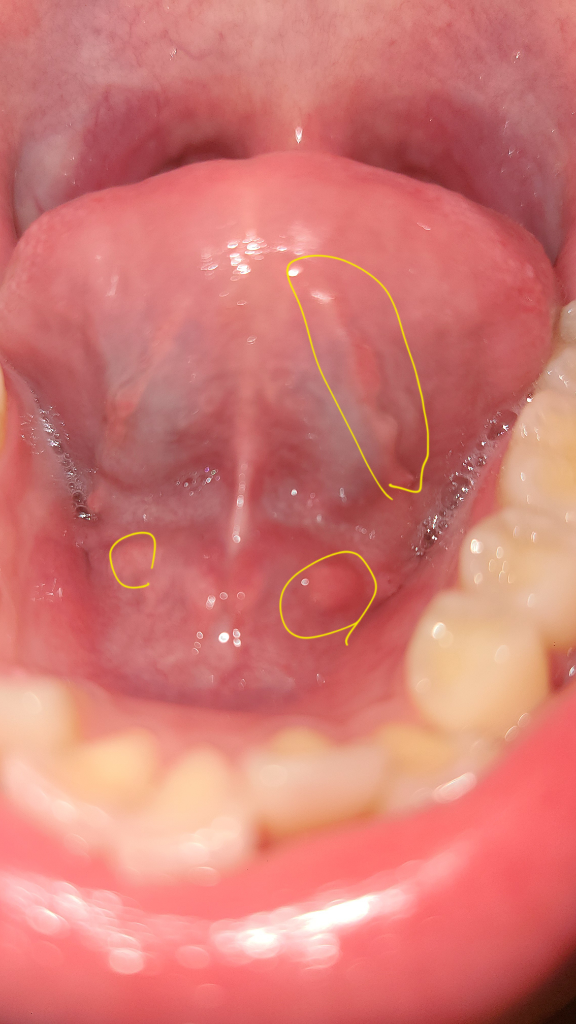

혀 밑에 이것들은 괜찮은 건가요?

오늘 혀 밑을 보니 뭔가 우둘투둘해서요.. 딱히 불편한 느낌은 없는데 정상적인 구조물들인가요?? 혹시 침샘에 문제가 생긴 건 아닌지 여쭙고 싶습니다 ㅠㅠ

• 1번 째 사진

• 안녕하세요. 채홍석 의사입니다. 혀 아래쪽에는 원래 울퉁불퉁한 부분이 있습니다. 침샘입구 혹은 혈관등이 지나가기 때문입니다.

정상적인 구조물이고 염증 등의 이상소견이 보이지 않습니다. 불편감이 없으시다면 그냥 지내셔도 괜찮습니다.